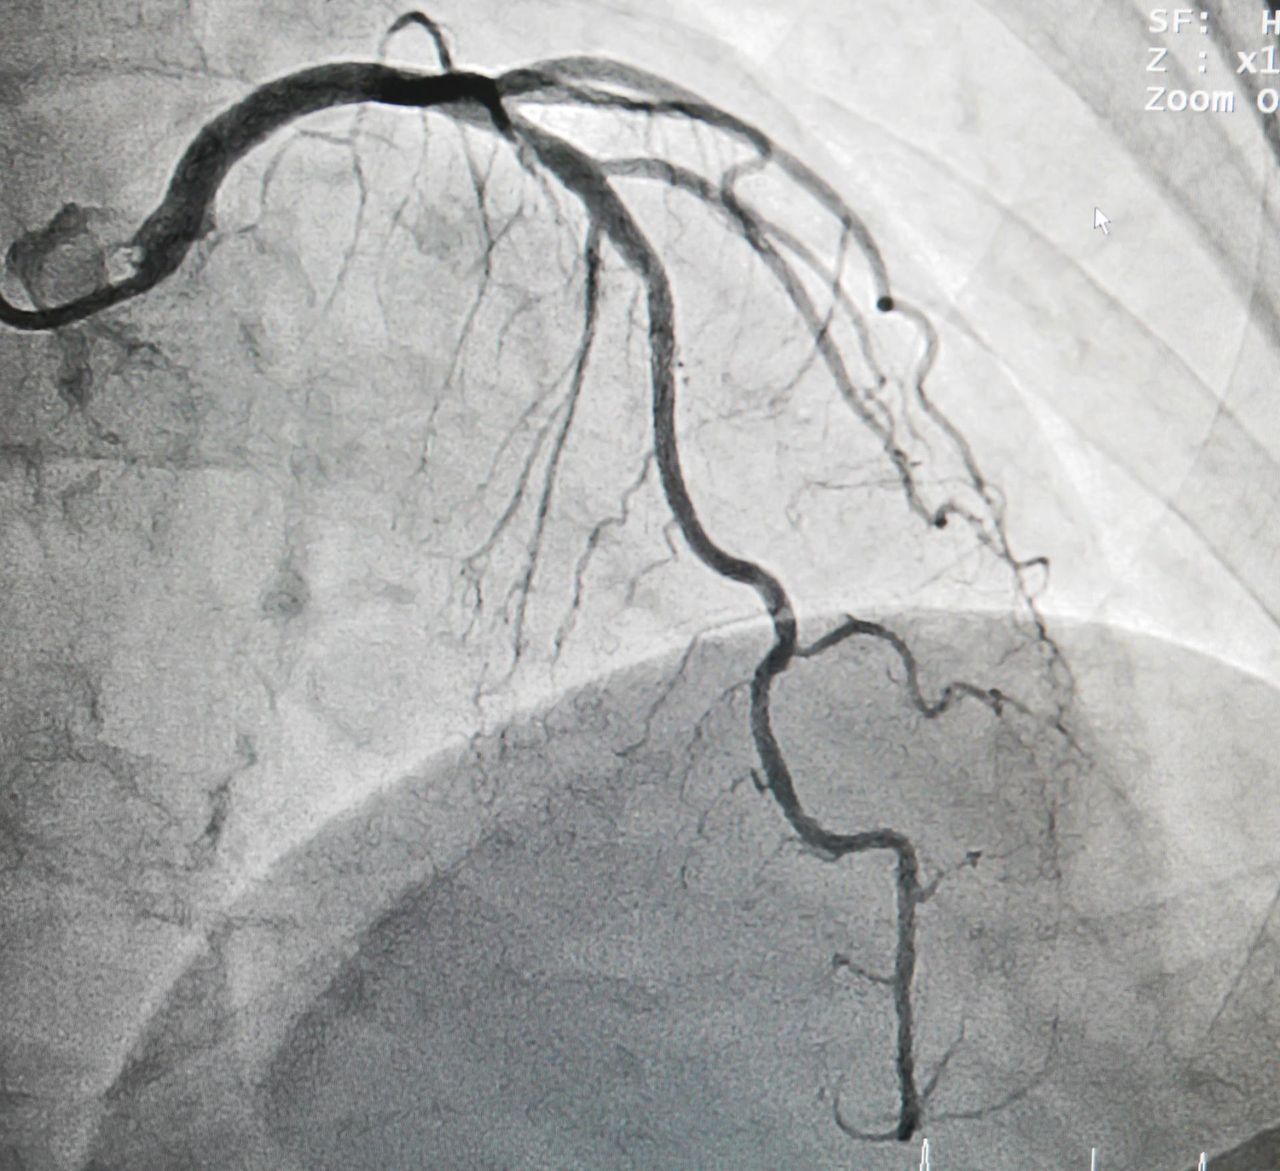

Przez lata nie daje o sobie znać. Lokuje się w ścianach krwionośnych i blisko osłabionej tętnicy. Mowa o tętniaku. To chodząca bomba – w każdej chwili może pęknąć i spowodować niebezpieczny krwotok, a w rezultacie śmierć. Zobacz, jakie są rodzaje tętniaków i gdzie się lokalizują.

Tętniak lokalizuje się w ścianach krwionośnych i blisko osłabionej tętnicy (123rf.com)Tętniak lokalizuje się w ścianach krwionośnych i blisko osłabionej tętnicy (123rf.com)